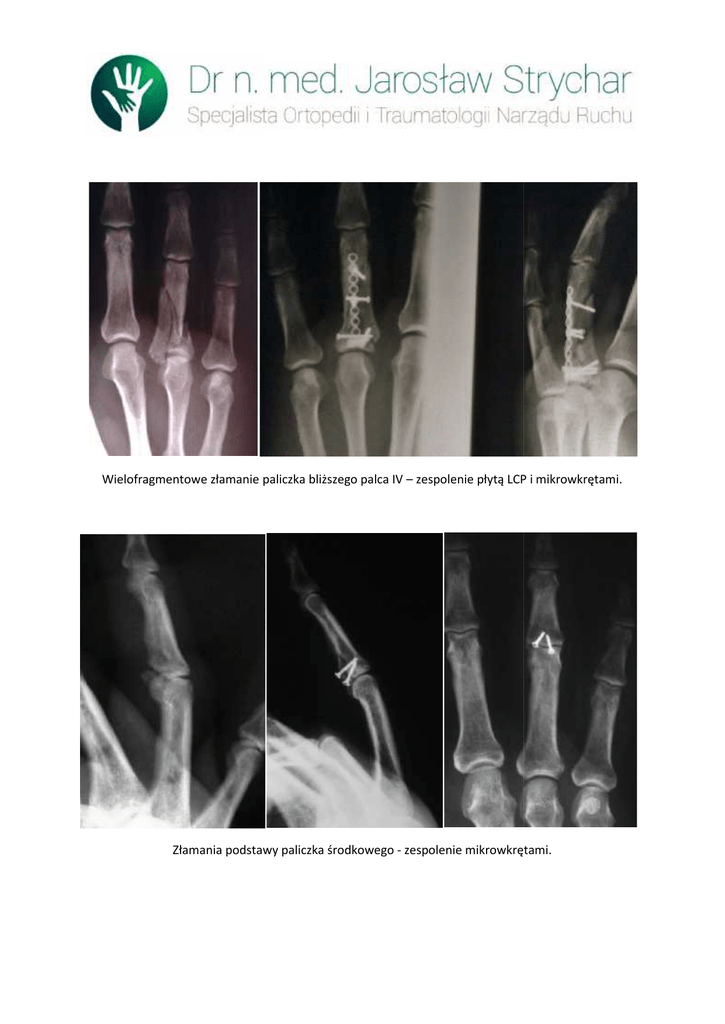

Złamania podstawy paliczka środkowego - zespolenie mikrowkrętami.